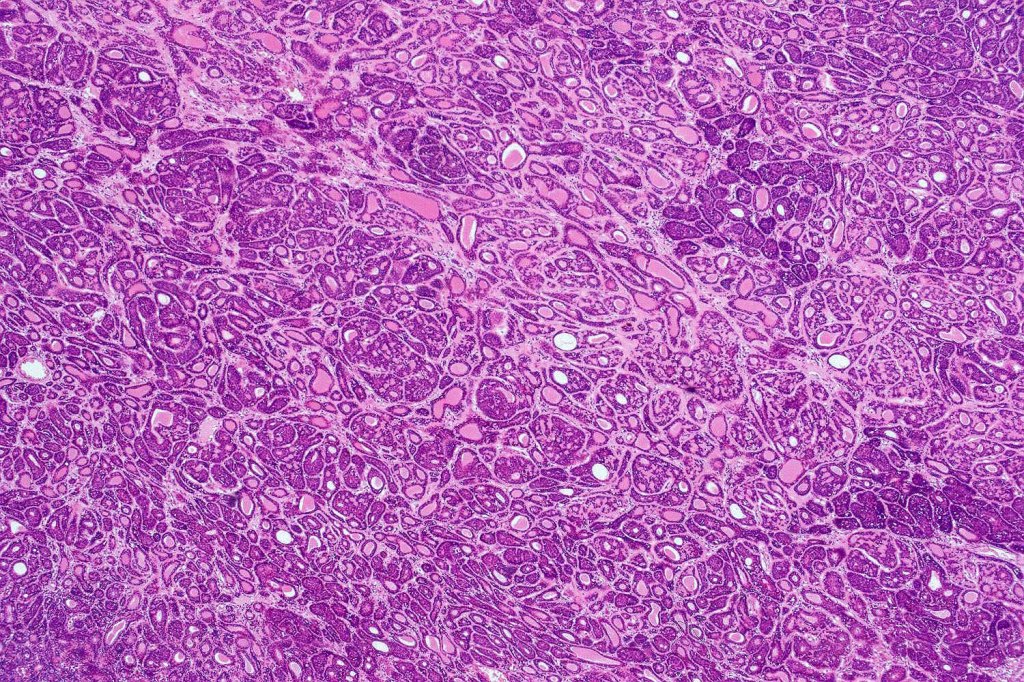

Histological features

•Dermal based

•Jigsaw/mosaic pattern arrangement of variably sized lobules of tumor cells with surrounding think, eosinophilic hyaline basement membrane

•Intralobular hyaline basement membrane material droplets

•Outer layer of intensely basophilic small cells surrounding larger central cells with pale staining or eosinophilic cytoplasm & vesicular nuclei

•Ductal differentiation